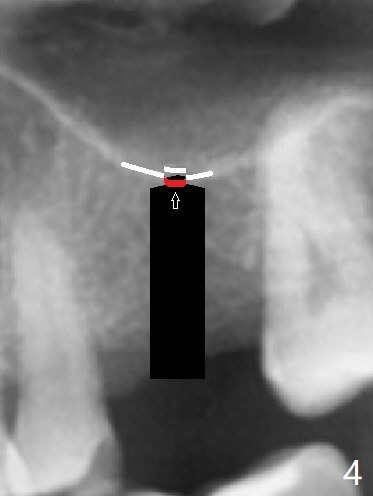

The guide is removed when the osteotomy at #14 (Fig.1 (8.45 mm bone height)) is finished in an under drilling manner in depth (Fig.2). The middle of the apical remaining bone is so thin (Fig.3 (white line representing the sinus floor)) that it can be pushed up like ping pong or eggshell (Fig.4 arrow). A 5x8.5 mm implant is placed with satisfactory insertion torque and depth, followed by insertion of a 6x3 mm healing abutment (Fig.5). There is mild resorption of the sinus floor distally 3.5 months postop, although the implant remains stable (Fig.6).